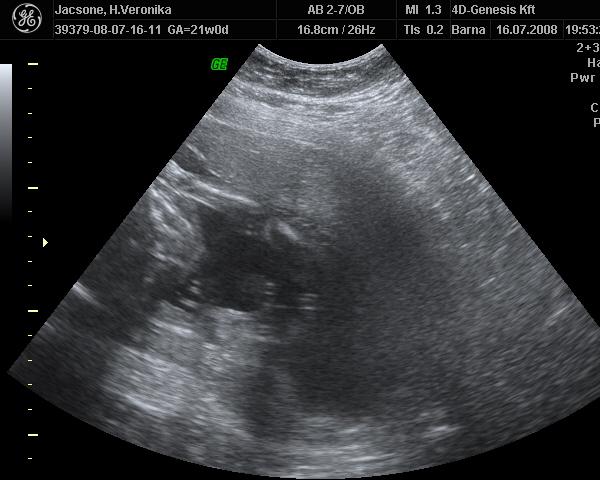

Képzeljétek, tegnap épp a Lotz Károly utcában jártam, és elcsábultam egy 4D-re :) Noel nagyon tündéri volt. Folyton a kukiját mutogatta :D Már 658 g!!! Nem sok az egy kicsit? Bár épp tele volt a pocija :)

Mi vasárnap voltunk újabb 4D-n, most már bizonyossággal mondták, hogy kisfiút várunk. Meg tudtam azt is, amit eddig nem értettem, hogy miért van ekkora minőségi különbség 4D és 4D között... A válasz a magzatvíz mennyiségében rejlik, a szaki elmondása szerint, minél több víz van jelen, annál kontúrosabb, élesebb a kép. Végülis logikus, de erre sosem gondoltam.